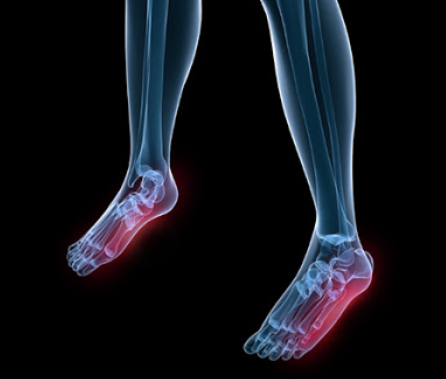

우리의 발바닥에는 근육이 있는데 그중 족저근막은 발뒤꿈치에서 시작해서 발바닥 앞쪽 5개 분지로 이어져 발가락 기저부에 부착되어 있는 강인하고 두꺼운 섬유띠를 말합니다.

족저근막은 발을 들어 올리는데 도움을 주는데 족저근막염은 바로 이 족저근막에 생기는 염증으로 발에 스트레스가 증가하거나 단기간 몸무게가 증가한다면 발병하기 쉬워지며 발의 모양상 오목발이나 평발이어도 발병률은 높아질 수 있습니다.